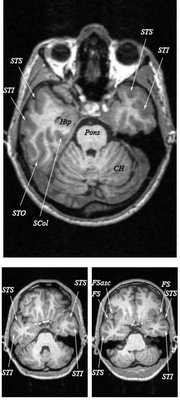

МРТ головного мозга. Т2-взвешенная аксиальная МРТ. Цветовая обработка изображения.

Знание анатомии мозга очень важно для правильной локализации патологических процессов. Ещё более важно оно для изучения самого мозга с помощью современных «функциональных» методов, таких как функциональная магнитно-резонансная томография (fMRI), и позитронно-эмиссионная томография. С анатомией мозга мы знакомимся ещё со студенческой скамьи и существует множество анатомических атласов, в том числе и поперечных сечений. Казалось бы, зачем ещё один? На самом деле, сравнение МРТ срезов с анатомическими приводит к множеству ошибок. Это связано как со специфическими особенностями получения МРТ изображений, так и с тем, что строение мозга очень индивидуально.

Представленная страница сайта основана на специальном изучении МРТ головного мозга здоровых лиц. Для этого изображения получали с минимальной величиной воксела (1 мм в каждом измерении), что исключало наслоения борозд. Каждая из структур прослеживалась в трёх реконструированных плоскостях путём её выделения с помощью компьютерной программы. Мы рассматривали различные анатомические варианты, что обсуждается в работе. В результате, учитывая вариабельность строения мозга, подобран условно «стандартный» мозг. Поскольку на сайте нереально представить 128 срезов в каждой из основных плоскостей, мы ограничились только каждым пятым срезом. Основные срезы в поперечной плоскости даны без наклона назад (угол 0º). Под ними для представления о изменении соотношения анатомических структур демонстрируются срезы, выполненные на тех же уровнях, но с наклонами назад -15º и -30º.

Поперечные (аксиальные) МРТ срезы головного мозга